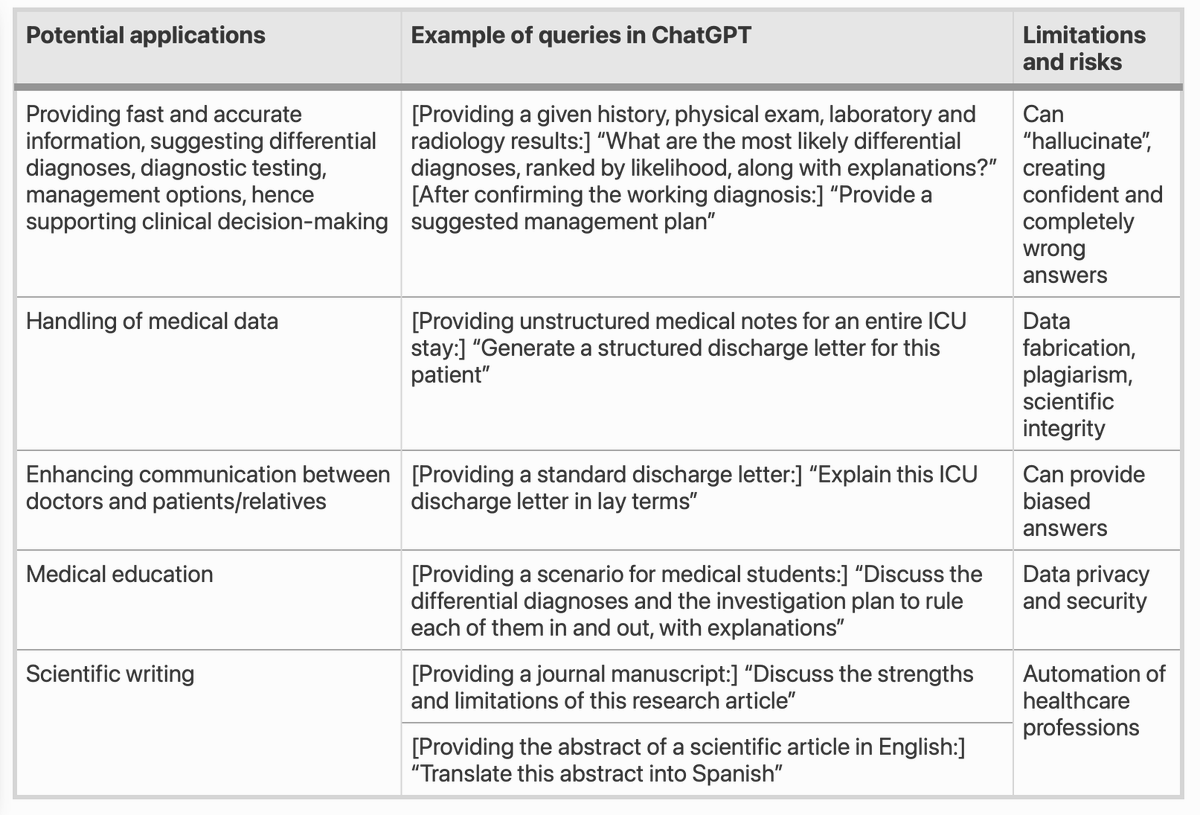

How could ChatGPT impact my practice as an intensivist? An overview of potential applications, risks and limitations Free read on Intensive Care Medicine at rdcu.be/ddusQ